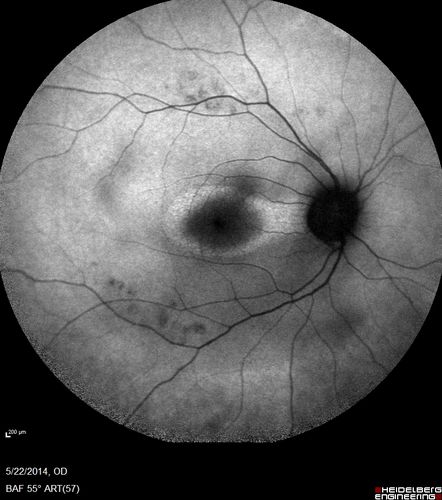

Retinitis Pigmentosa Sine Pigmento